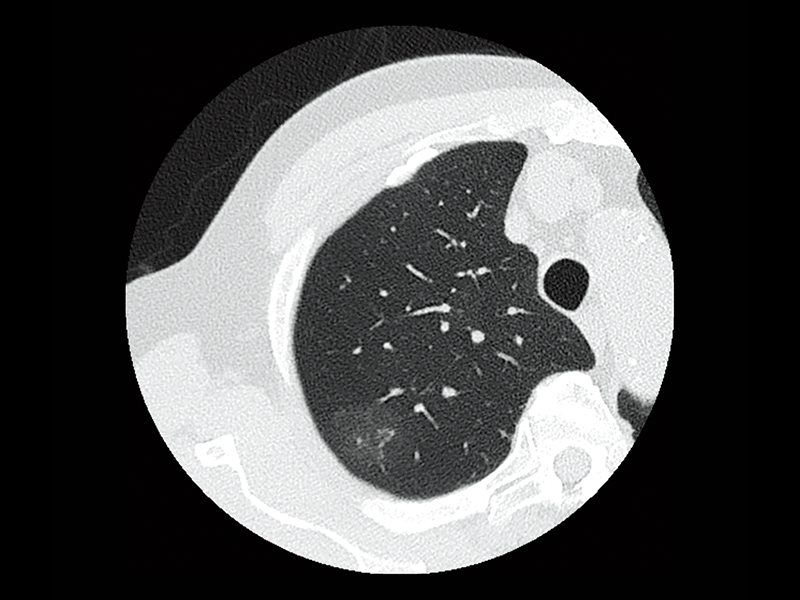

Interstitial pneumonia

Lung screening (CTDlvol: 2.0 mGy)

Non-tuberculous mycobacteria